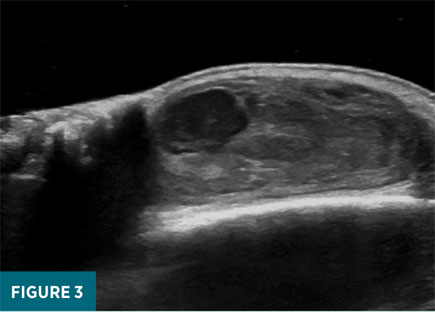

Initial duplex ultrasound examination of the right frontal scalp revealed a 1.6 X 2.7 X 2.7 cm well-circumscribed, heterogeneously echogenic mass just deep to the dermis (Figure 2). Grayscale images revealed turbulent pulsatile motion within the lateral aspect of the mass, and color Doppler interrogation revealed a “see-sawing” region of internal Doppler flow measuring 1.2 X 1.0 cm (Figures 3-5). These findings were consistent with a pseudoaneurysm of the right frontal scalp with a component of solid hematoma and an actively bleeding region represented by the area of see-sawing Doppler flow. The patient was referred to vascular surgery, and his apixaban therapy was halted. After discussion with the surgeon, a plan was made to follow up with duplex ultrasound in one week to assess for interval change. Ultrasound performed six days later revealed an approximately stable-in-size (1.4 X 2.2 X 2.8 cm) hematoma with an interval decrease in the region of internal Doppler flow (0.5 X 0.6 cm compared with 1.2 X 1 cm). The patient remained off anticoagulation and a final follow-up ultrasound performed 19 days later revealed an interval decrease in maximal size of the pseudoaneurysm to 2.1 cm (previously 2.8 cm) with lack of internal color Doppler flow compatible with complete thrombosis.

While standard, grayscale ultrasound evaluation of a pseudoaneurysm can reveal a cystic, hypoechoic bulging structure abutting a blood vessel, this finding is not specific and can also be associated with simple hematomas, as well as simple or complex cysts.8 Thus, more conclusive diagnosis frequently requires color and spectral Doppler analyses. Color Doppler ultrasonography characterizes directional blood flow by measuring the relative frequency of sound waves emanating from blood flowing within a region of interest. Arterial blood flow directed toward the ultrasound probe will be represented with an orange-red color, while blood flowing away from the probe will be blue, owing to the lower relative frequency of its associated sound waves.9 In the setting of a pseudoaneurysm, bidirectional internal flow within the cystic-appearing pseudoaneurysmal space results in a “swirling” pattern of red and blue signal, reminiscent of the yin-yang Chinese philosophical symbol.

Much like the classic B-mode, grayscale findings mentioned above, the “yin-yang sign” is not necessarily specific to pseudoaneurysm: noncommunicating hematomas that have not fully thrombosed may also display internal flow, owing to force transmission from pulsations within the adjacent artery.10 Thus, conclusive diagnosis requires spectral Doppler analysis, which results in a graphical display of local flow velocity. In the setting of a pseudoaneurysm, spectral Doppler over the neck of the pseudoaneurysm will reveal a “to-and-fro” signal, in which systolic positive flow velocity (ie, flow into the pseudoaneurysmal sac) alternates with diastolic negative flow velocity back into the now relatively low-pressure artery.